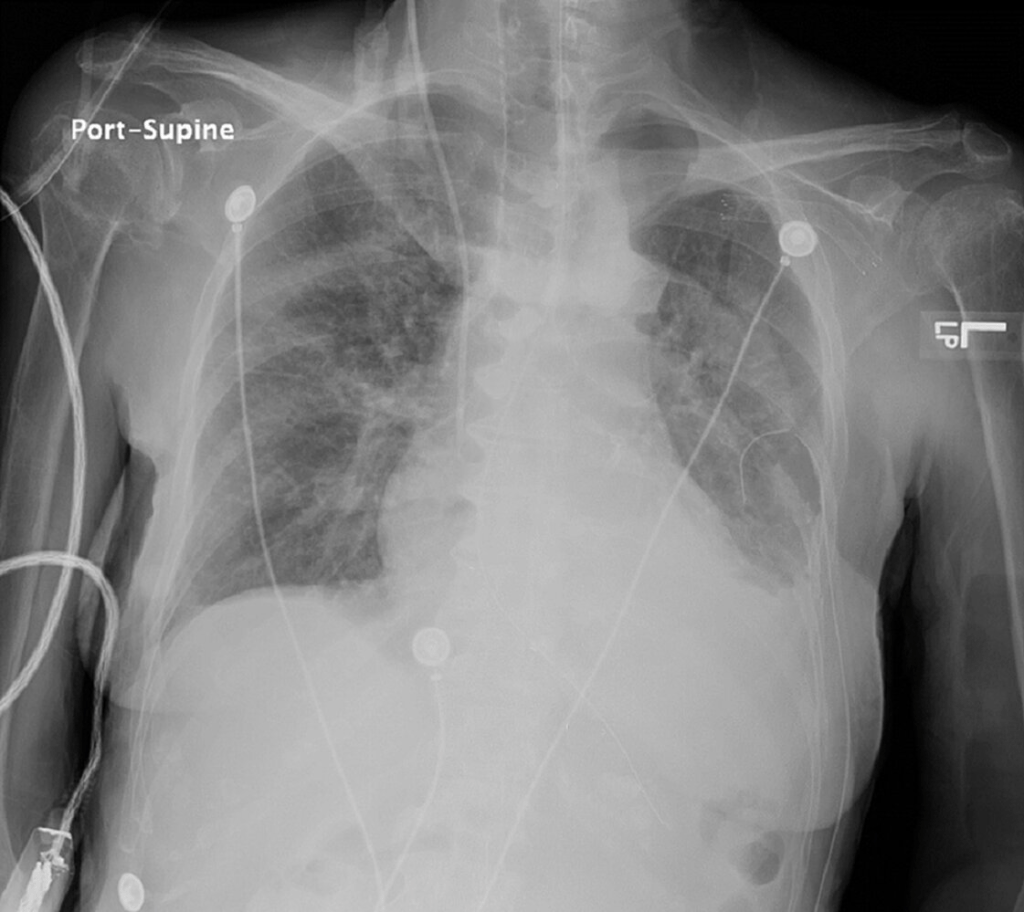

- Obtención de una radiografía de tórax y/o abdomen

Obtenga una radiografía de tórax y/o abdomen para confirmar la colocación antes de administrar medicamentos o nutrición.

En la radiografía de tórax , una sonda nasogástrica colocada correctamente cruzará el diafragma en la línea media y terminará debajo del hemidiafragma izquierdo.